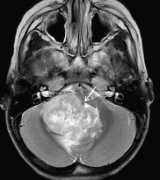

听神经瘤 是一种良性的,通常生长缓慢的肿瘤,由供应内耳的平...